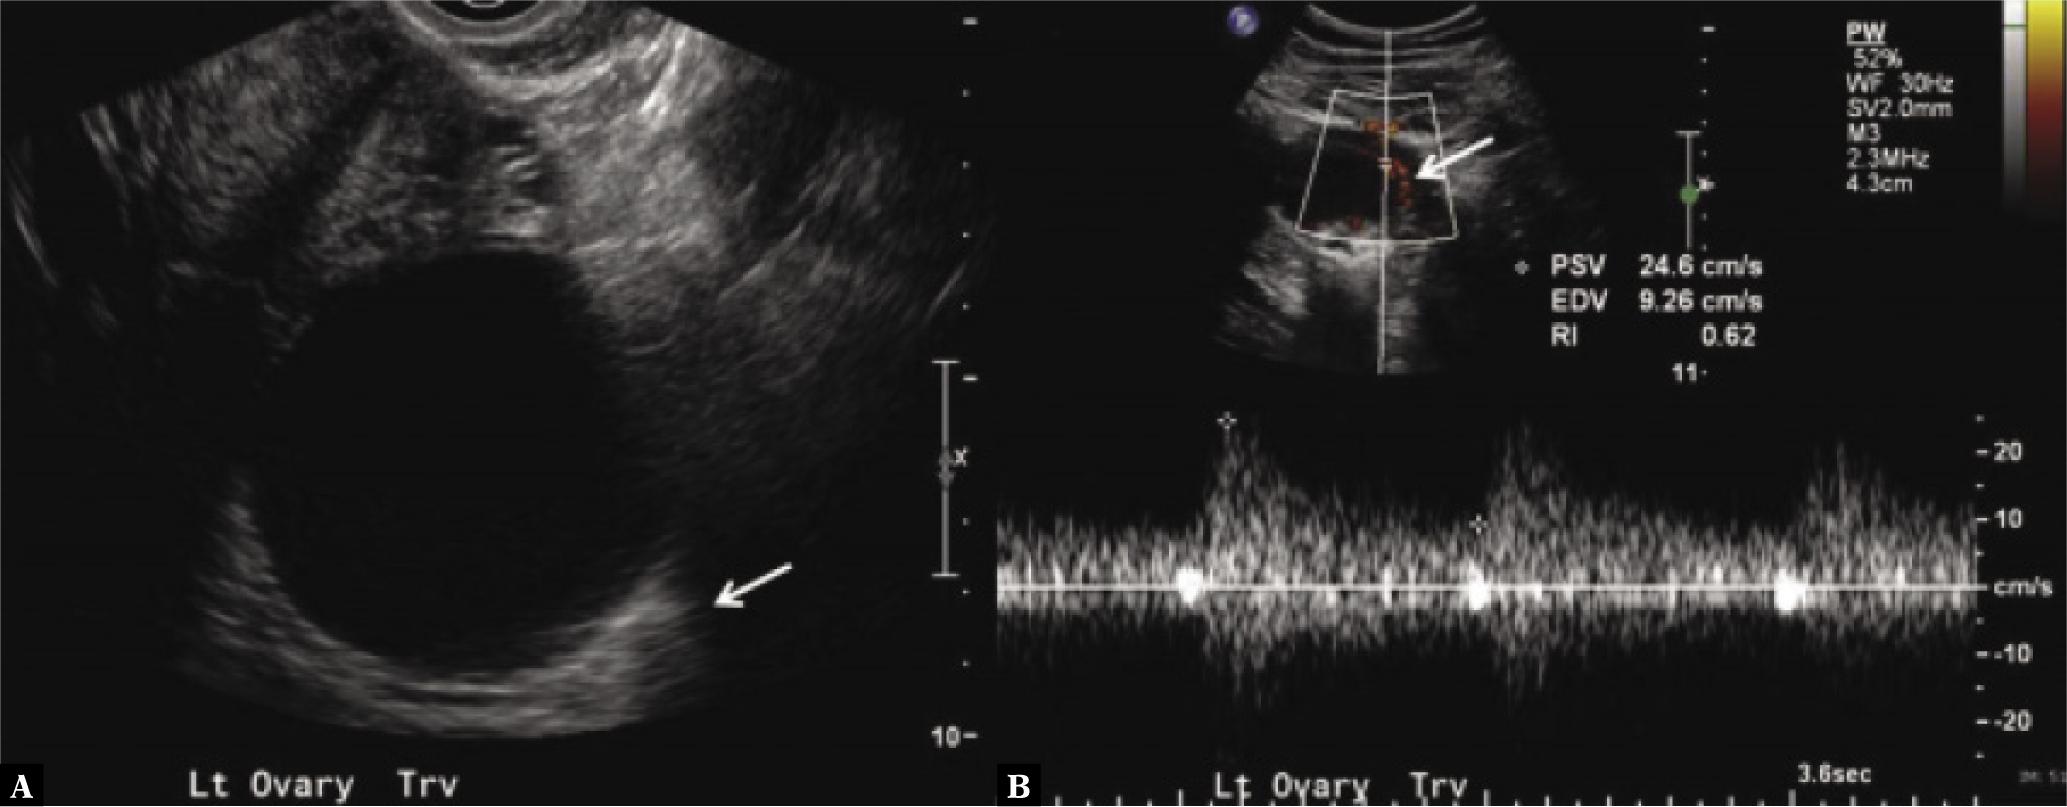

Fig. 4.